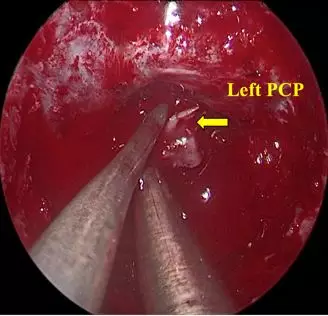

• Remove leftside Posterior Clinoid Process